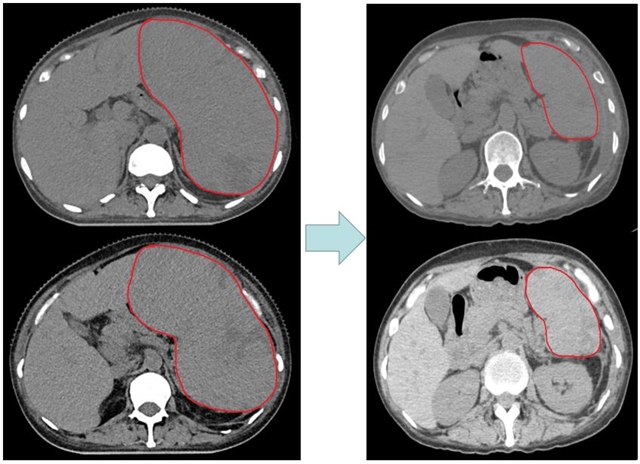

“患者刚入院的时候挺着个大肚子,像是怀胎10个月似的。”主管医生李阔回忆着说道。通过CT检查,结果提示张女士的脾脏明显增大,最大直径已达20.5cm。

2022年3月10日,医生开始对张女士的“巨脾”进行放疗。放疗过程中,脾脏快速缩小。

肿瘤·血液病科(城北病区)副主任兼肿瘤放疗中心主任庞军教授说:“为了让肿瘤得到精确照射,减少对其周围正常器官的照射,我们为患者缩野(随着肿瘤缩小放疗照射范围跟着缩小)2次。”

28次放疗结束后,张女士原来的“大肚子”消失了。治疗半年后多复查CT,脾脏大小恢复正常。